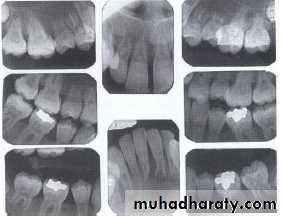

Dentin dysplasia, type I. panoramic & periapical films of the same case show the short and poorly developed roots, obliterated pulp chambers and root canals, and periapical inflammatory lesions.

Dentin dysplasia, type II. panoramic &periapical films of the same case show obliteration of the pulp chamber, reduction in the caliber of root canals, and pulp stones obscuring the flame-shaped pulp chambers.

Periapical inflammatory lesions are associated with some of the mandibular anterior teeth.